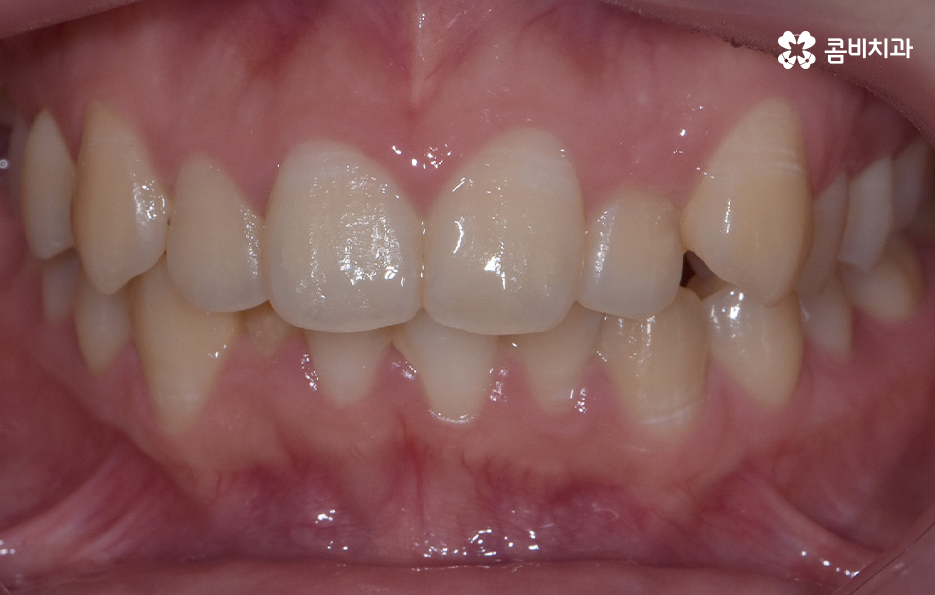

오늘 덧니 비발치 교정 사례로 보시는 환자분의 경우에는 윗니와 아랫니 앞니 부분에 조금씩 덧니가 있는 상태로 덧니를 제외하면 대체적으로 치열 상태는 고른 편이며 덧니 교정 사례 중에서는 돌출입도 함께 개선해야 하는 경우가 많지만 위 환자분의 경우에는 돌출입의 정도가 양호했고 입술라인 역시도 정상 범위에 가까웠기 때문에 발치를 필요로 하지 않았지만 치아의 이동 공간과 보다 자연스러운 입술라인 그리고 얼굴형과의 조화를 고려하여 악궁 확장과 어금니 후방 이동을 적절히 활용하여 교정 치료가 진행되었다고 볼 수 있어요